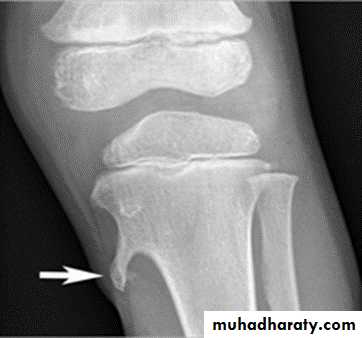

Solitary bone cyst:

Age: young adults & children.Site: long bones.

Findings: well-defined expanding lytic lesion.

A piece of cortical bone has broken off and descended through the serous fluid contained within the lesion and can be seen in the dependent portion of the lesion (arrow) as

a fallen fragment sign.

A fallen fragment sign is said to be pathgnomonic for

a unicameral bone cyst

Fallen fragment sign